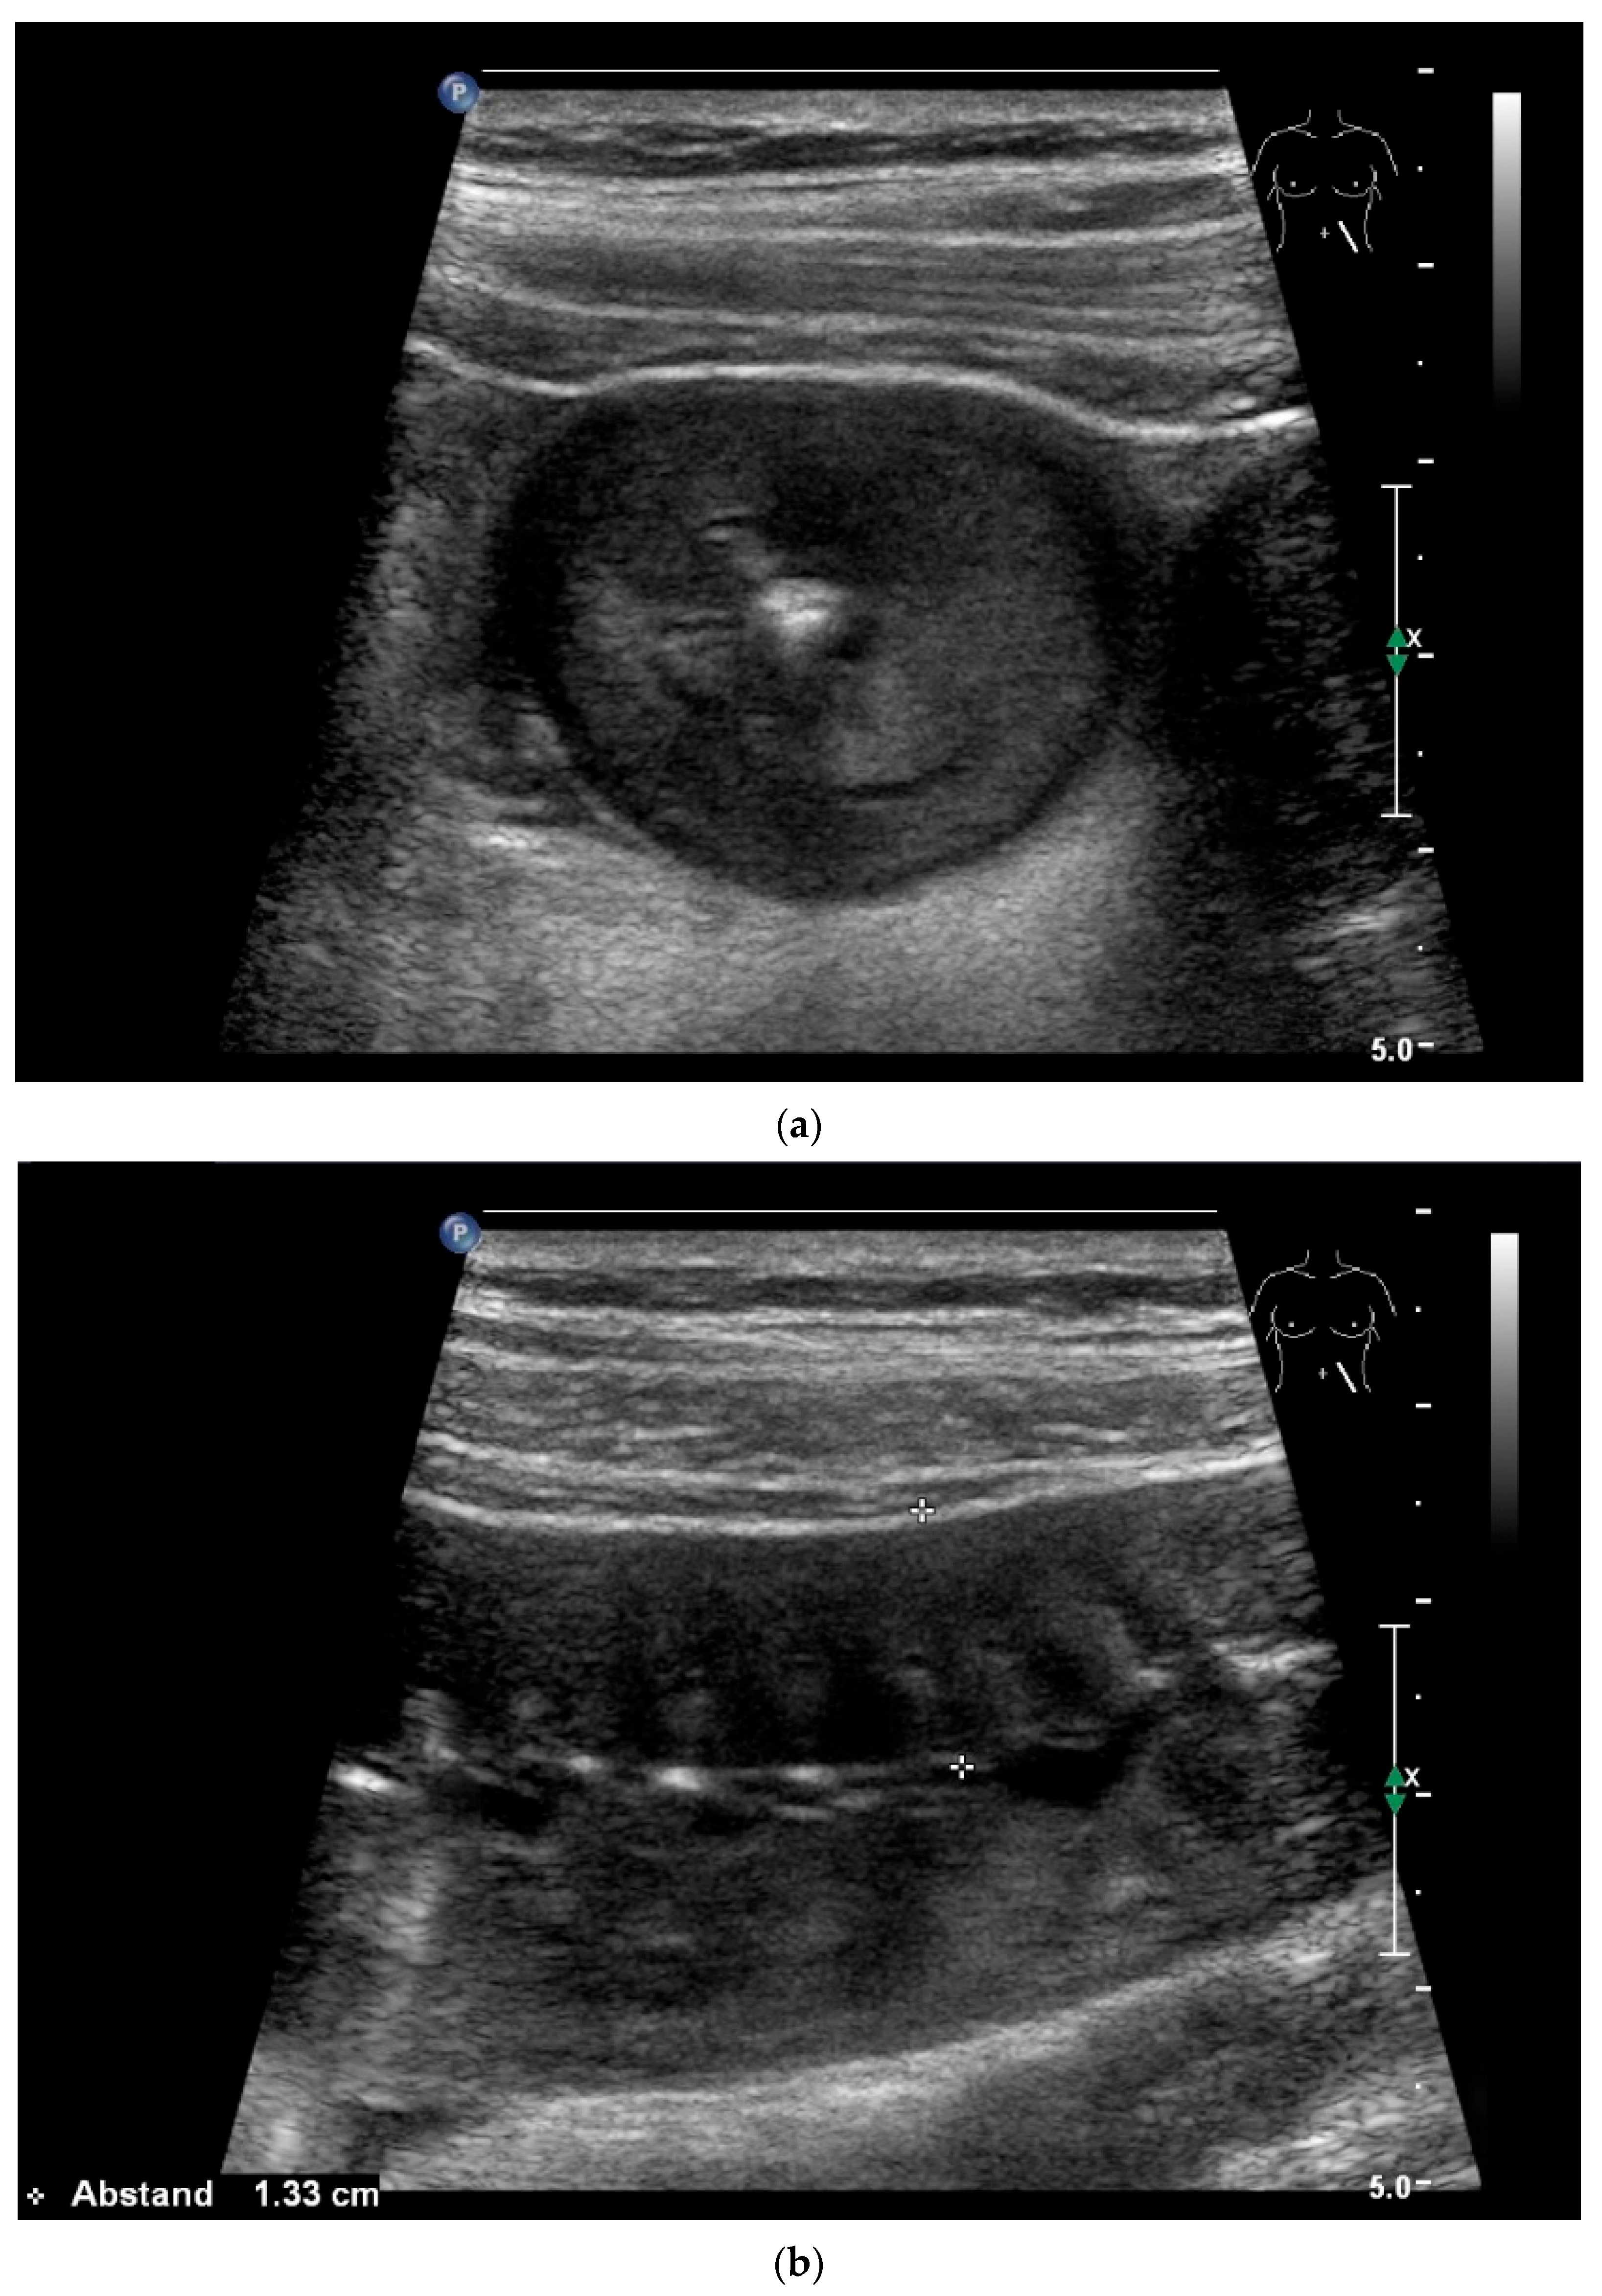

8.8. Imaging of Lymphomas

- Hasaballah, M.; Abdel-Malek, R.; Zakaria, Z.; Marie, M.S.; Naguib, M.S. Transabdominal ultrasonographic features in the diagnosis of gastrointestinal lymphoma. J. Gastrointest. Oncol. 2018, 9, 1190–1197. [Google Scholar] [CrossRef]

- Goerg, C.; Schwerk, W.B.; Goerg, K. Gastrointestinal lymphoma: Sonographic findings in 54 patients. Am. J. Roentgenol. 1990, 155, 795–798. [Google Scholar] [CrossRef]

- Zhang, X.Y.; Zhang, B.; Cai, S.; Jiang, Y.X.; Li, W.B.; Yang, X.; Zhao, R.N. Ultrasonographic and general pathologic features assessment of small intestinal lymphoma. Zhongguo Yi Xue Ke Xue Yuan Xue Bao 2013, 35, 318–321. [Google Scholar] [CrossRef]

- Cui, N.Y.; Gong, X.T.; Tian, Y.T.; Wang, Y.; Zhang, R.; Liu, M.J.; Han, J.; Wang, B.; Yang, D. Contrast-enhanced ultrasound imaging for intestinal lymphoma. World J. Gastroenterol. 2021, 27, 5438–5447. [Google Scholar] [CrossRef]

| Lymphoma | Very pronounced wall thickening with marked hypoechogenicity. Large regional and distant lymph nodes. Look for splenic infiltration. Tumor vessels on CDI and hyperenhancement on CEUS. Heterogeneous hyperechogenicity of the mesentery with walling of the mesenteric vessels. Multiple localizations are possible. |